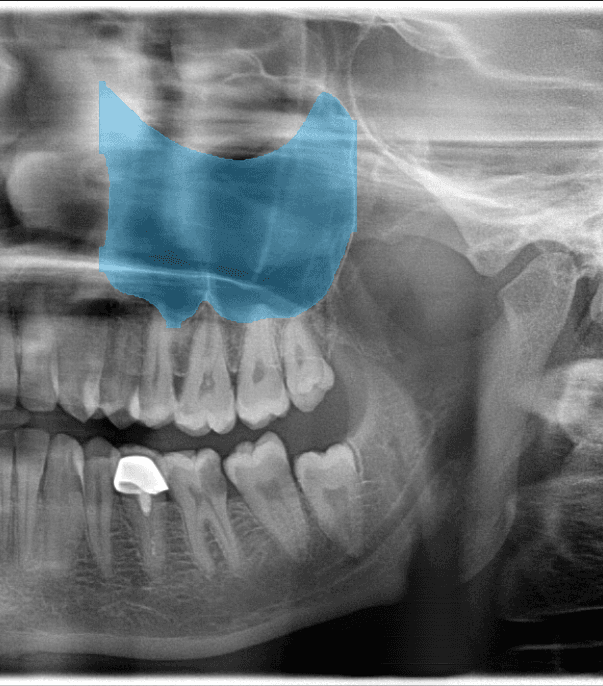

Anatomy marker

Bone segmentation

01Anatomy DetectionMay mark IAN canal, mental foramen, maxillary sinus boundaries, and root apices for clinician review

02Bone SegmentationMay support clinician review of bone levels and possible horizontal or vertical defect patterns

03Sinus DetectionMay highlight sinus boundaries and possible patterns for clinician review in planning context

05Soft Tissue InsightsMay highlight candidate calcification, asymmetry, or soft-tissue-region observations for clinician review